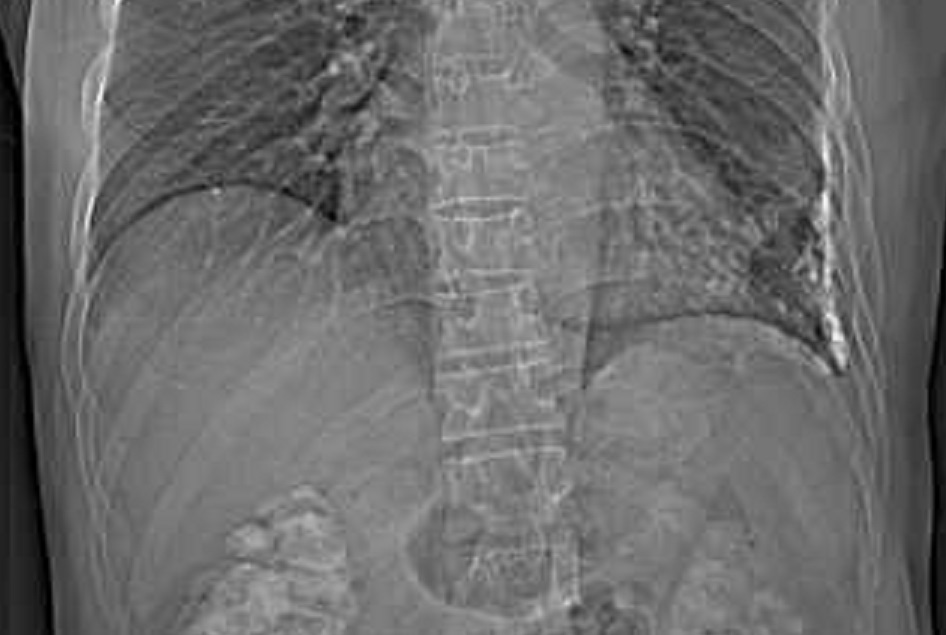

Image

radiolologique cliche de face PA d'une epaissisement

pleural diffuse du poumon droit par consequence de

tuberculose du poumon droit . Aspect radiologique

est opacite en plaque de tres densite s'étend et

recouvre tout le poumon droit , Poumon droit en

fibrose restrictive |